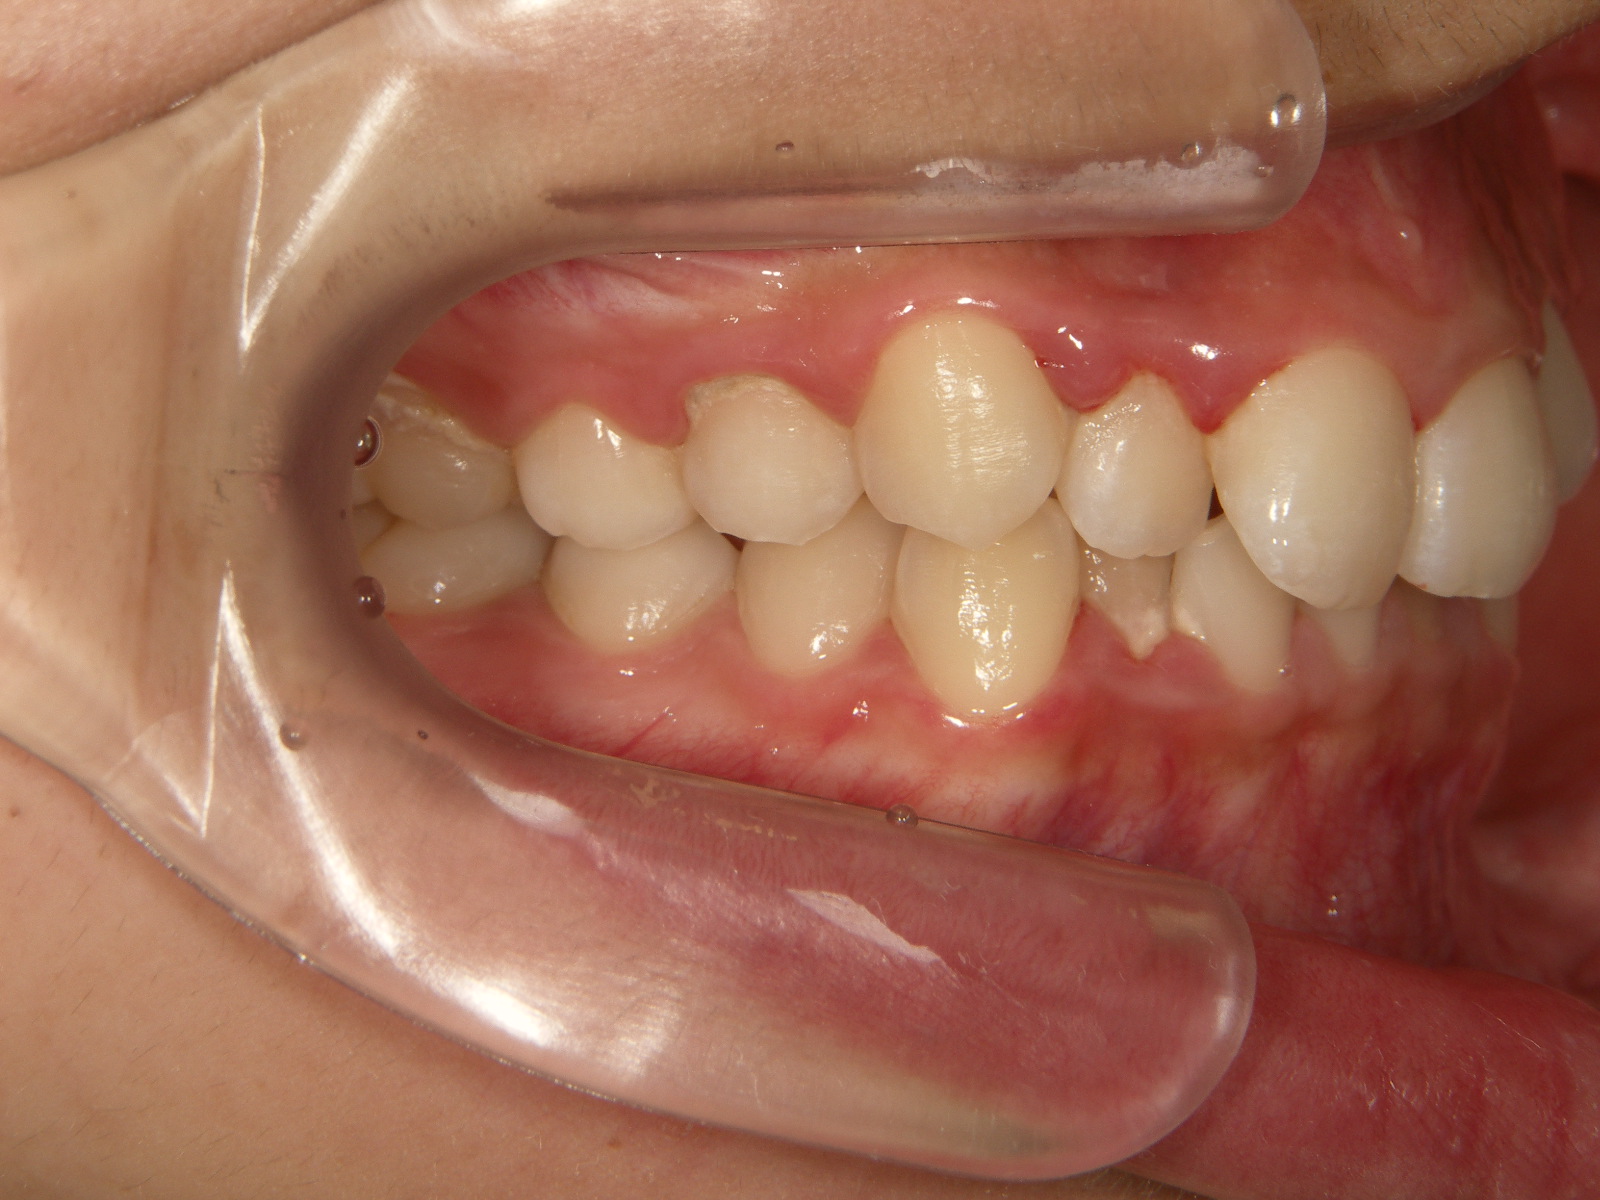

過蓋咬合の原因と重症度によって、使用する矯正装置の種類が決まります

過蓋咬合(またはオーバージェット)の原因、重症度、症状によって、どのタイプの矯正器具を使用するのが最適かが決まります。

過蓋咬合にはどのような種類の矯正装置が最適ですか?

これらのタイプの矯正装置は金属またはセラミックで作られています。それぞれの歯に装着され、ワイヤーで繋がれています。これにより、口の上部と下部の両方の曲がった歯が整列し、まっすぐになります。歯がまっすぐになったら、コイル、スプリング、バンドを追加します。これらを組み合わせることで、顎を正しい位置に移動して整列させることができます。

従来の矯正装置は自宅で取り外すことができず、通常は 1 ~ 3 年間装着されます。この期間中、歯科矯正医は通常は 1 か月ごとに、必要に応じてブレースを調整し、締めます。

従来の矯正装置は、長期間にわたって歯に一定の一貫した圧力を加え、歯を最適な位置にゆっくりと移動させます。従来の矯正装置は自宅で取り外すことができないため、ほとんどの種類の過蓋咬合を矯正する最も迅速かつ効果的な方法です。